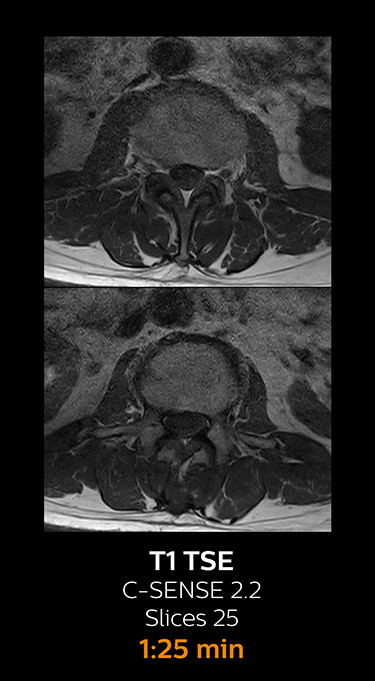

Fast MRI of lumbar spine

With Compressed SENSE, the scan time for the routine lumbar spine examination at KNC was reduced from 11:41 to 8:17 minutes,

which corresponds to 34% reduction.

MRI examination of lumbar spine with Compressed SENSE

MRI examination of the lumbar spine with Compressed SENSE

Ingenia 3.0T CX

Scan time 8:17 min. (was 11:41 min. without Compressed SENSE)